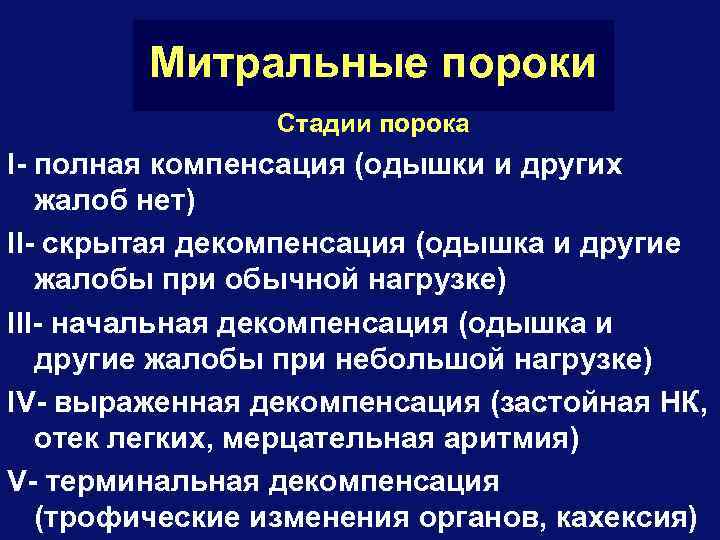

Митральные пороки Стадии порока I- полная компенсация (одышки и других жалоб нет) II- скрытая декомпенсация (одышка и другие жалобы при обычной нагрузке) III- начальная декомпенсация (одышка и другие жалобы при небольшой нагрузке) IV- выраженная декомпенсация (застойная НК, отек легких, мерцательная аритмия) V- терминальная декомпенсация (трофические изменения органов, кахексия)